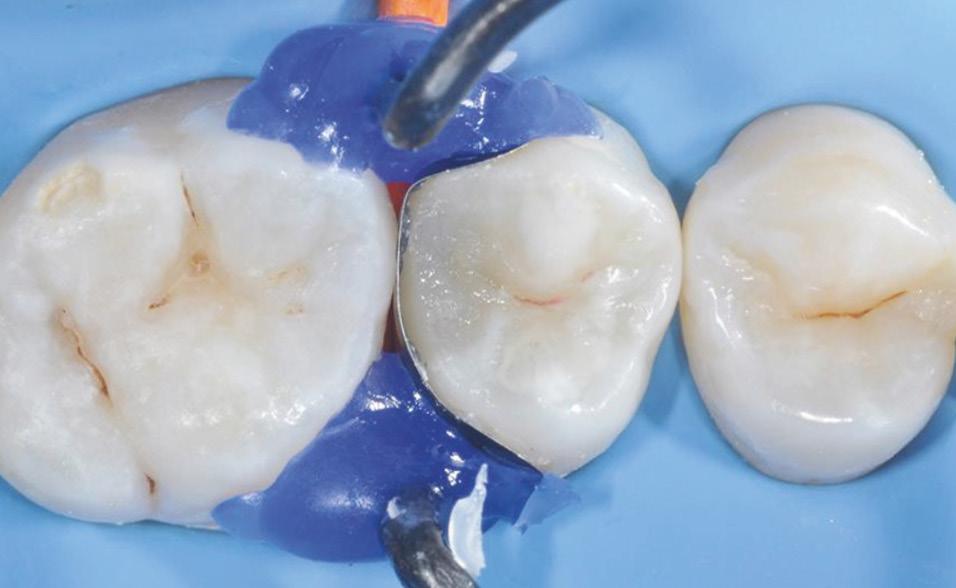

Fig. 5: Caries removal and cavity preparation. Caries detection dye was used as a Fig. 6: A 15 second selective enamel etch using 3M™ Scotchbond™ Universal Etchant followed by rinsing and air drying. Fig. 7: 3M™ Scotchbond™ Universal Adhesive was scrubbed into the preparation for 20 seconds followed by air-drying and light-curing with 3M™ Elipar™ LED Curing Light for 10 seconds.* Fig. 8: 3M™ Filtek™ One Bulk Fill Restorative A3 was placed in one increment. The composite was cured for 10 seconds on the occlusal surface.*

Fig. 9: After removal of the matrix band, the composite was cured for 10 seconds on both the buccal and lingual surface.* Fig. 10: After finishing and pre-polishing, the 3M™ Sof-Lex™ Diamond Polishing System on moist surface was used to create a high gloss polish.